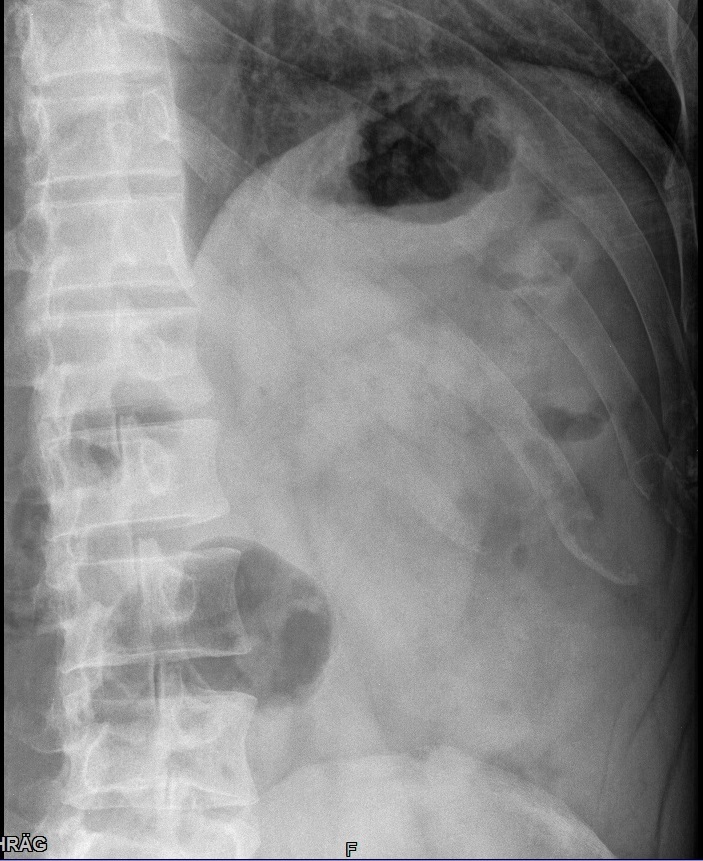

Rippen 7-9 werden vom Kassettenrand abgeschnitten. Eine Beurteilung ob die Kortikalis intakt ist, kann hier nicht getroffen werden.

Patient besser auf der Kassette lagern und schauen, dass beim Atemkommando nicht die Rippen über die Kassette ragen. Sollte das alles nichts bringen evtl. auch auf eine größere Kassette zurückgreifen.